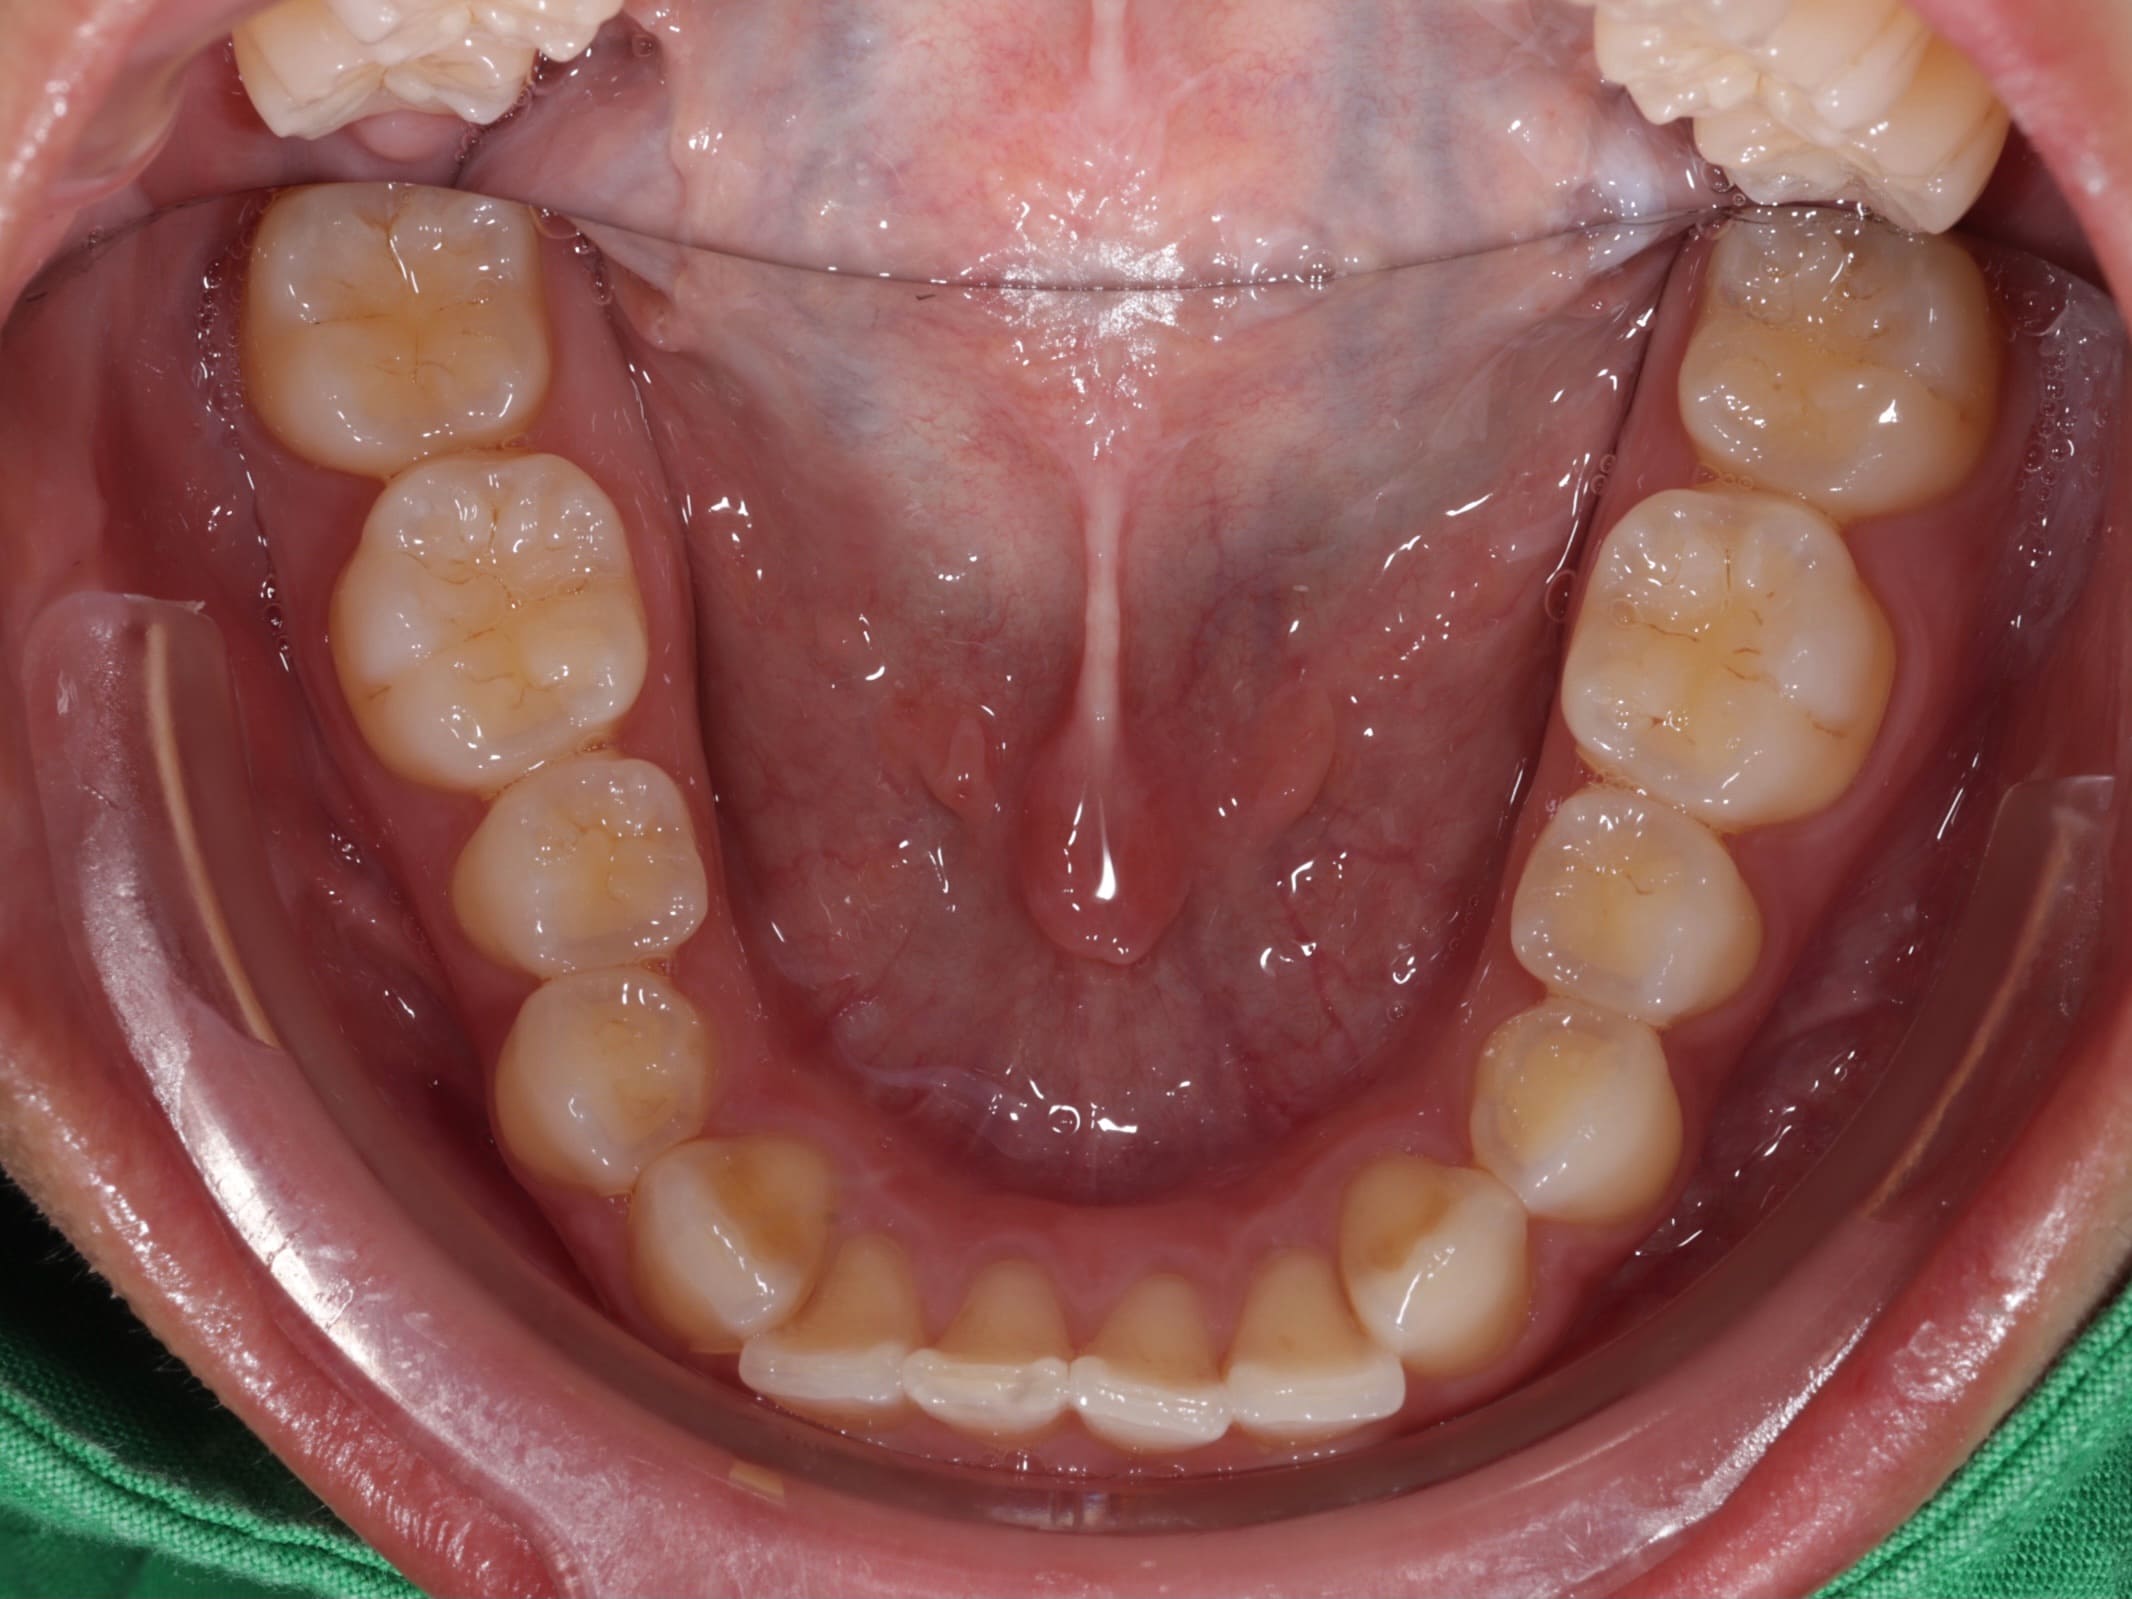

經過仔細檢查後,我們發現病患的口腔狀況存在幾個需要處理的問題。首先是左上方的臼齒因為嚴重蛀牙只剩下牙根,導致兩側的牙齒失去支撐而逐漸傾倒,進而影響了整體的牙齒排列。另外,下排牙齒有錯咬的狀況,造成下巴看起來往前凸。除此之外,由於病患本身的牙齒比例偏短,笑的時候牙齦露出的面積相對比較多,影響了整體的美觀性。

針對這些問題,我們擬定了完整的治療方案。首先,利用矯正的方式,將後方的第二大臼齒和智齒慢慢往前移動,填補缺牙的空間,同時調整上下排牙齒的咬合關係,讓錯咬的情況回復到正常的咬合狀態。當矯正治療完成後,病患的狀況其實已經改善了許多。